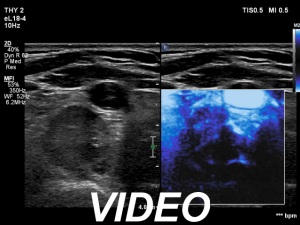

Second examination 6 month later (2nd row of images)

Clinical presentation. The patient was referred for evaluation of hyperparathyroidism. Elevated calcium and parathyroid hormone levels were found during the first evaluation. (These findings were not yet available when I first examined the patient.) Further evaluation disclosed a hyperfunctioning right lower parathyroid. The patient was operated on but no parathyroid tissue was found on histopathology. (A more experienced parathyroid surgeon was quarantined at the scheduled time of the operation, so a less experienced colleague performed the surgery.) Both hypercalcemia and hyperparathyroidism have persisted.

Palpation: no abnormality.

Laboratory tests: parathormone 129 pg/ml (normal value: 12-88), serum calcium 2,89 mM/L, phosphate 0,71 mM/L.

Ultrasonography revealed a hypoechoic mass corresponding to the right lower parathyroid.

Cytology resulted in benign lesion, a pattern which corresponded to a parathyroid adenoma.

The patient was reoperated and histopathology disclosed a parathyroid adenoma according to the right lower parathyroid.